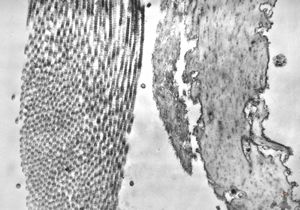

M,41y. | ribosome-lamella complex in tricholeukocyte -hairy cell leukemia, spleen

M,41y. | ribosome-lamella complex in tricholeukocyte -hairy cell leukemia, spleen